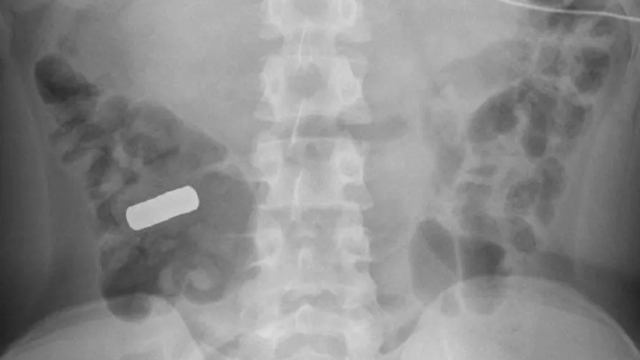

Um adolescente, que não teve a identidade revelada, foi operado às pressas ao ser identificado cerca de 21 ímãs em seu estômago e intestino. O caso inusitado veio à tona em uma publicação da revista científica BMJ Case Reports, o relato foi feito por médicos de uma faculdade norte-americana.

O rapaz chegou até o hospital com cólicas abdominais severas. Após exames de radiografia e tomografias computadorizadas foi revelado a presença de um item metálico no estômago do menino. Ele, entretanto, não se recordava de ter ingerido os objetos que estavam em abundância.

A suspeita é que ele tenha ingerido durante uma crise de sonambulismo. Foi realizada uma endoscopia, no exame os médicos identificaram três discos empilhados, cada um com cerca de 8 milímetros de largura. Os discos eram, na verdade, ímãs super fortes, por conta do longo tempo no local, os ímãs estavam formando uma úlcera na parede do estômago.

Eles foram removidos através da endoscopia, entretanto, exames posteriores mostraram a presença de mais objetos. Outros três foram removidos com uma colonoscopia, exame semelhante à endoscopia, mas no caso feito através dos anus. Os demais tiveram que ser removidos em cirurgia.

O caso era tão grave que alguns objetos tinham formado buracos nas paredes do aparelho digestivo. O jovem passa bem, e segundo investigação dos médicos sobre como os ímãs foram parar no local, a família disse acreditar que a ingestão ocorreu durante um episódio de sonambulismo.